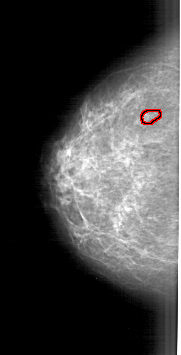

A_1905_1.LEFT_MLO

FILE: A_1905_1.LEFT_MLO.OVERLAY

TOTAL_ABNORMALITIES 1

ABNORMALITY 1

LESION_TYPE CALCIFICATION TYPE PLEOMORPHIC DISTRIBUTION CLUSTERED

ASSESSMENT 4

SUBTLETY 3

PATHOLOGY MALIGNANT

TOTAL_OUTLINES 1

BOUNDARY